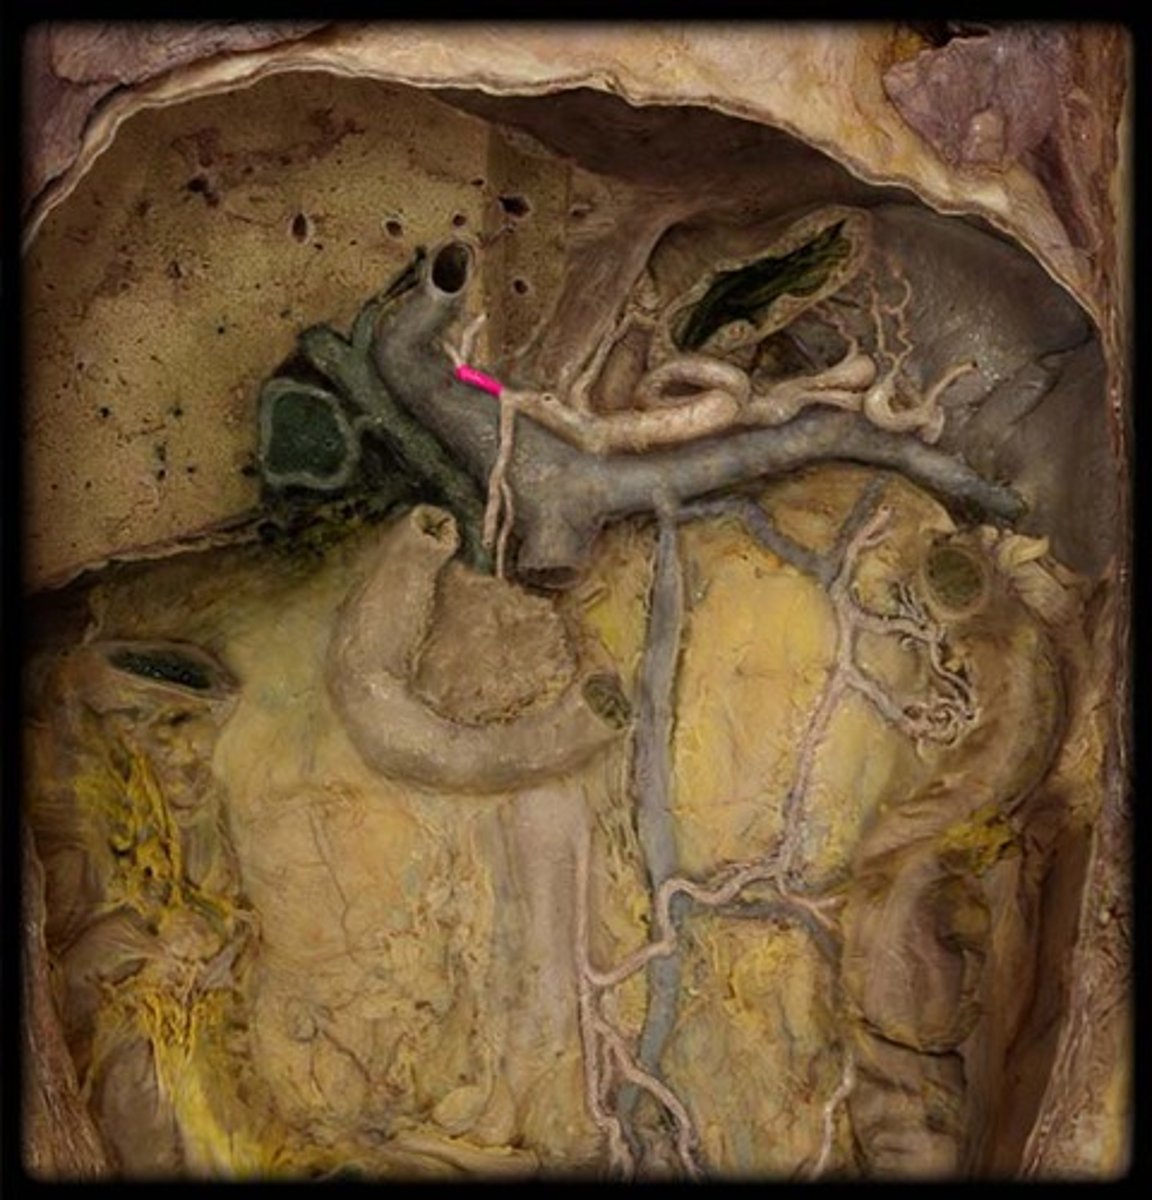

portal triad

what is in this structure

hepatic artery proper

common bile duct

common hepatic duct

cystic duct

hepatic portal vein